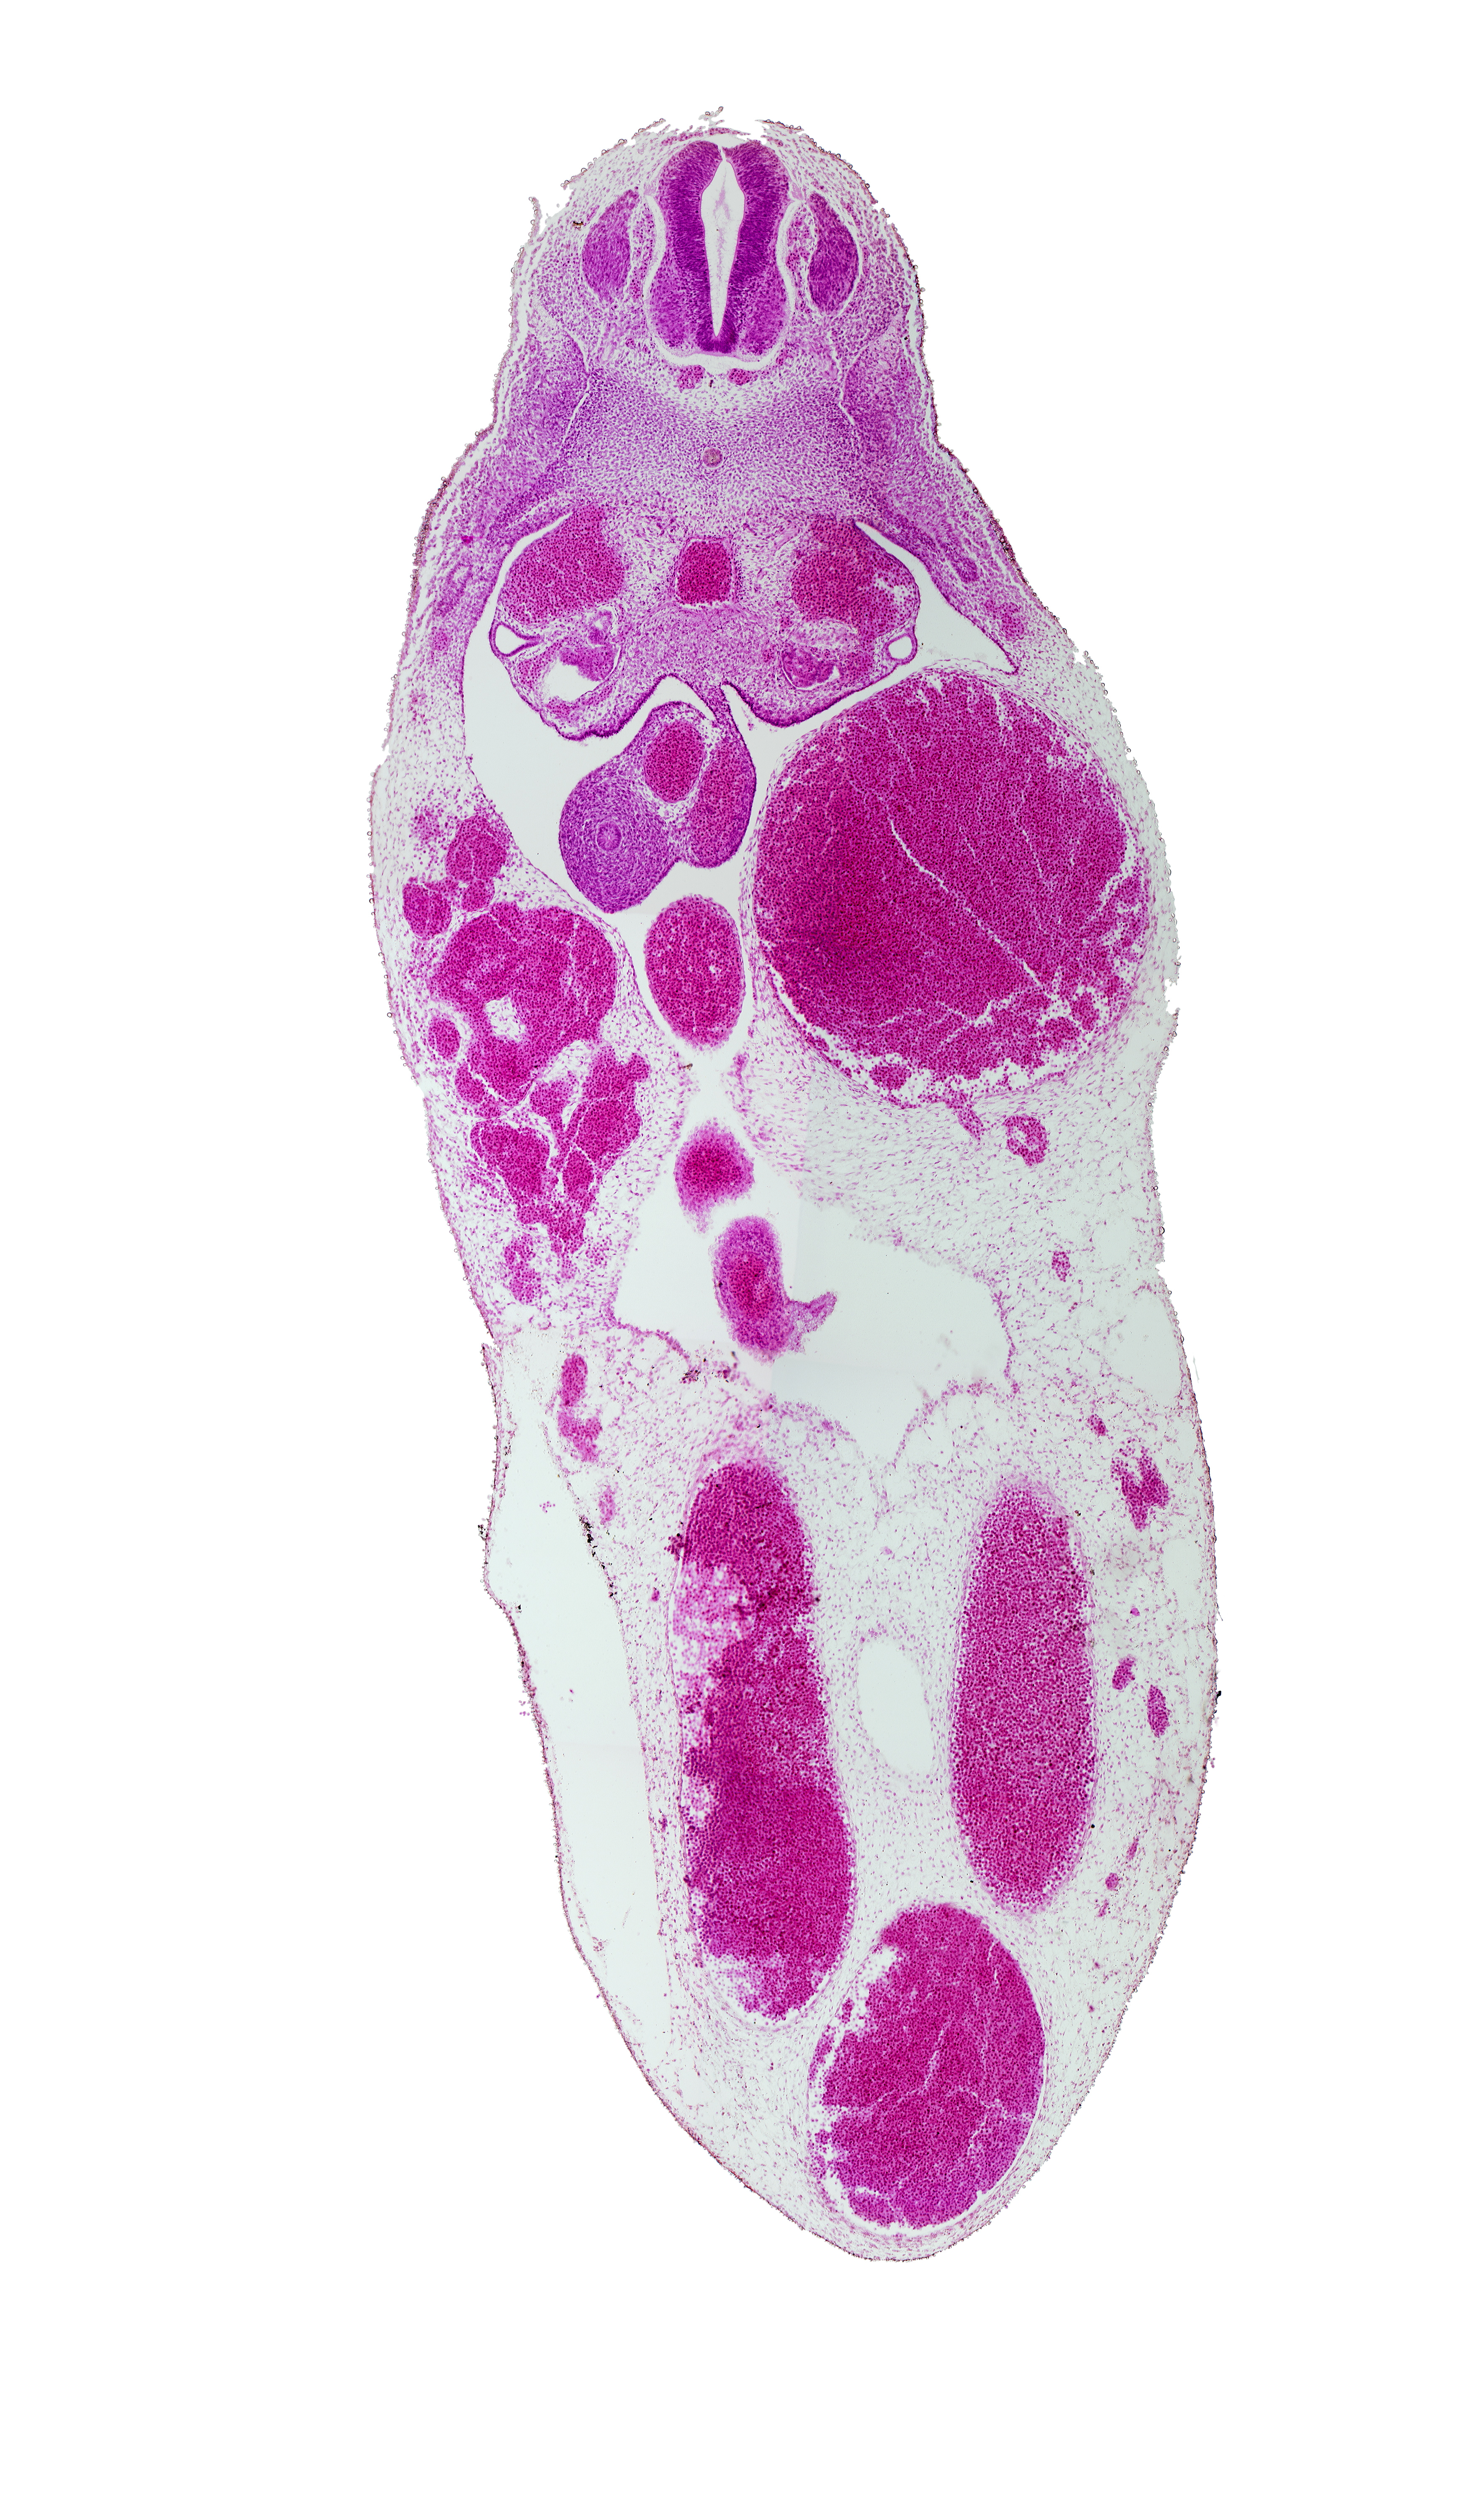

Carnegie Embryo #721 | Location: 20-01-03

Keywords: T-7 spinal ganglion, aorta, junction of peritoneal cavity and umbilical coelom, left umbilical artery, left umbilical vein, mesonephric duct, midgut, midgut umbilical intestinal loop, notochord, postcardinal vein, right umbilical artery, superior mesenteric artery, umbilical coelom, umbilical vein, vitelline (omphalomesenteric) vein

Source: The Virtual Human Embryo.